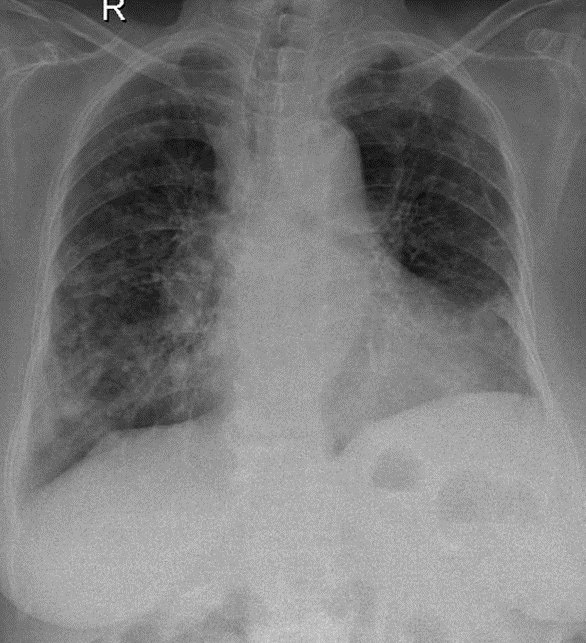

Hãy phân tích tình huống Nữ 84 tuổi CĐ:Suy hô hấp, viêm phổi cộng đồng nặng

1-Thâm nhiểm phế nang lan tỏa hai phổi (P)>(T) => VIÊM PHỔI